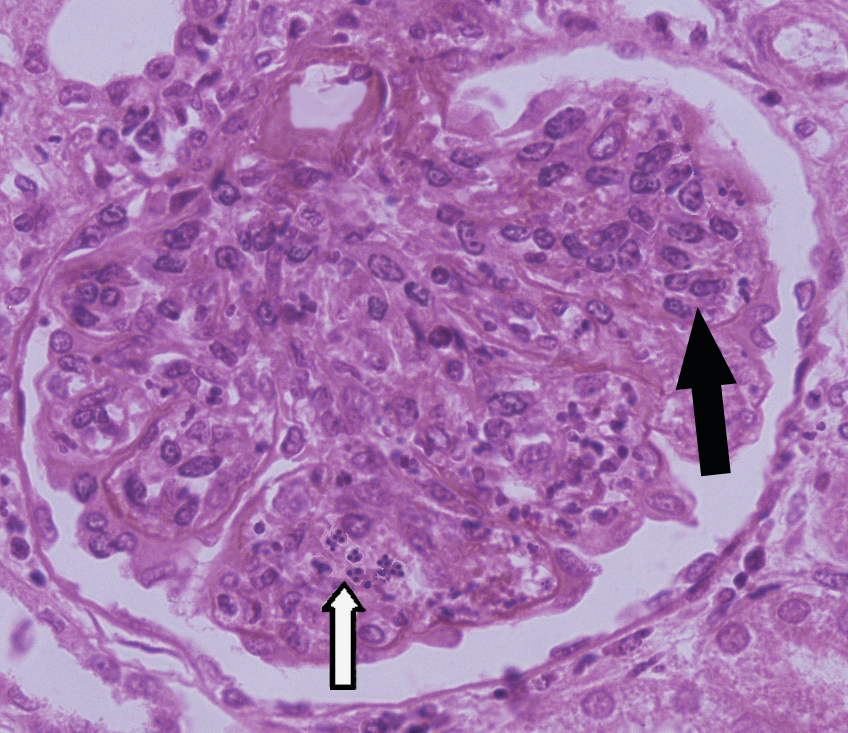

1.急性肾小球肾炎